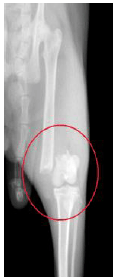

治療前のレントゲン写真です。 太ももを正面から見た図ですが、骨が折れているのが分かります。(赤丸) |

![]() |

治療2ヵ月後のレントゲン写真です。 折れた骨が正常な位置でしっかり固定されているのが確認出来ます。 治療後、この子は痛みも無く元気に走り回っています。 |